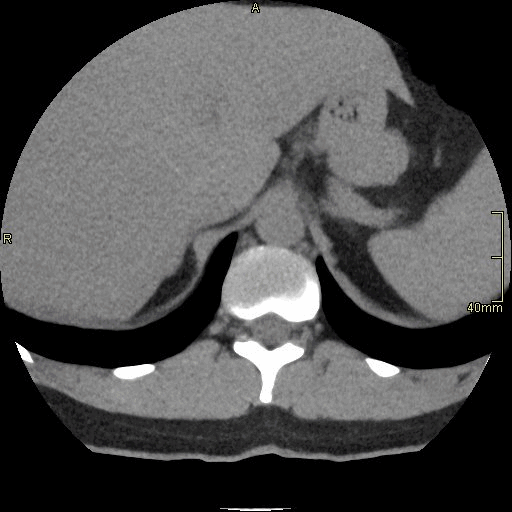

CT Lumbosacral Spine Non Contrast- Soft Tissue window (axial)